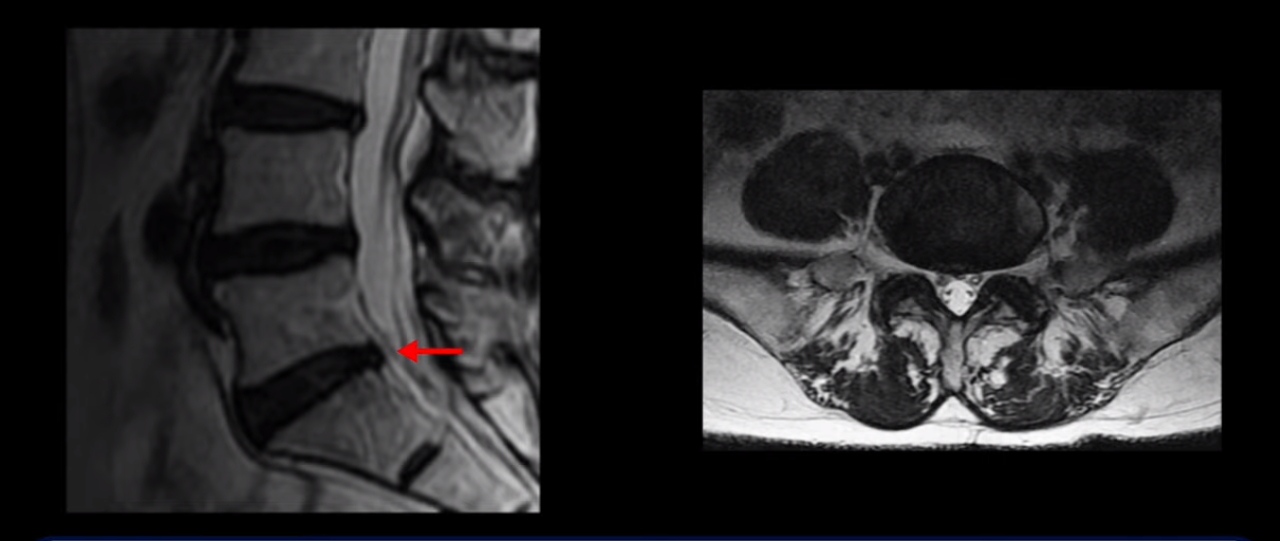

이분 MRI를 보시면 허리 세 마디가 퇴행은 있으나

척추관도 3번 4번

4번 5번

5번 1번

전부 다 충분히 넓고 왼쪽 다리 쪽으로 신경이 나가는 추간공도 전부 다 충분히 넓은 상태입니다.

신경이 눌려 보이지 않는 겁니다. 그러니까 수술 후 MRI를 보고 모든 병원이 전부 다 ‘수술은 잘돼 있다’, ‘아무것도 해줄 게 없다’ 그냥 기다리라고만 얘기했다고 합니다. 신경외과, 정형외과, 재활의학과가 서로 다른 과로 전과시키면서 다들 아무것도 해줄 게 없다고 하니 희망을 잃은 상태였다고 했습니다.